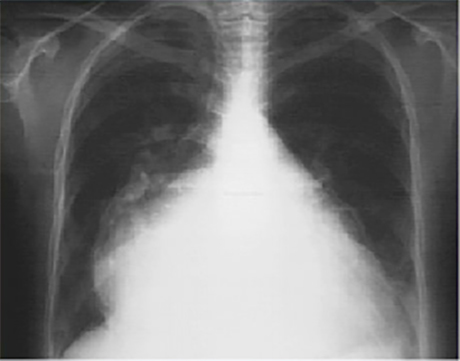

PA

These chest X rays show marked left atrial enlargement.

In this PA view, the marked left atrial enlargement is demonstrated by the atrial appendage along the left heart border, and is so massive, that it also comprises the right heart border.

Such a giant left atrium may be seen in severe, chronic mitral regurgitation.